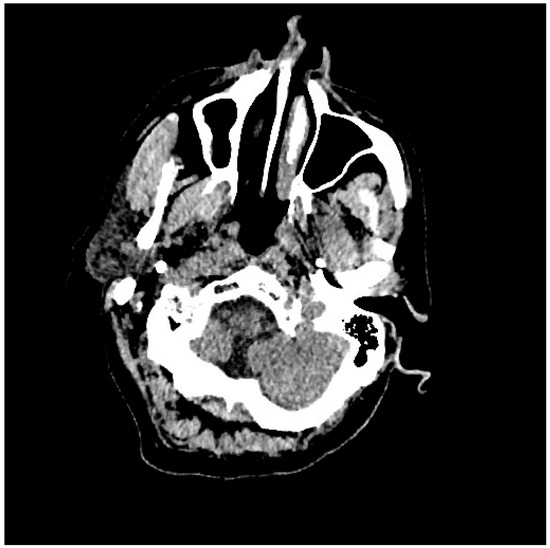

| Pt 7, M, 71, 2025 | HHD, cognitive involutional syndrome | High fever, headache, confusion, worsening motor difficulty with lower limb weakness | +/+ | Neg | Neg | Neg | ICH of the occipital horns of the lateral ventricles (Figure 2) | Diffuse meningoencephalitis, with involvement of the cauda extremity roots. ICH of the occipitopolar and bihemispheric mid-posterior cingulate sulci, the left temporoparietal carrefour, and the fourth ventricle, occipital horns, and pericerebellar cistern. Posterior dorso-lumbo-sacral, anterior dorso-lumbar (up to L1), and sacral epidural hematoma (Figure 3 and Figure 4) | DEX, Igs | Gradual clinical improvement, however lower limb weakness persisted | Transferred to a rehabilitation facility 34 days after hospital admission. | |

Figure 3.

Evidence of ICH on brain CT scan (Table 1, patient 7).

Three male patients with a median age of 71 years (range 68–74), presented ICH associated with WNE (Table 1, patient 2, 7, 9). Two male patients, the first 74-year-old (Table 1, patient 2) suffering from arterial hypertension and the second 68-year-old (Table 1, patient 9) suffering from diabetes mellitus and post-ischemic dilated heart disease, died after 13 and 21 days, while the third patient (Table 1, patient 7) was transferred to a neuromotor rehabilitation facility after 34 days of hospitalization. This patient, before admission to the hospital, presented age-related brain involution symptoms and suffered from chronic hypertensive heart disease. The reasons for admission to the emergency room were worsening motor difficulties with weakness in the lower limbs, a rapidly worsening state of confusion, high fever, and an episode of hypertensive peak. Repeated studies of the brain and spinal cord, using computed tomography (CT) scans and magnetic resonance imaging (MRI), have documented a very complex picture, characterized by diffuse meningoencephalitis, with a diffuse flogistic involvement of the pachy-leptomeninges and the equine cauda roots, blood deposits in the occipitopolar and bihemispheric mid-posterior cingulate sulci, the left temporoparietal carrefour, the fourth ventricle and occipital horns and the pericerebellar cistern. There was also evidence of a diffuse posterior dorso-lumbo-sacral, anterior dorso-lumbar (up to L1) and sacral spinal cord epidural hematoma. Diffuse hemosiderin coating was present on the dural surface in the dorso-distal posterior lumbo-sacral and anterior lumbo-sacral regions, as well as at the anterior 8th-10th level. Serology for WNV was positive, while WNV RNA testing in CSF, blood, and urine was negative. Treatment included two 5-day cycles of high-dose immunoglobulins and the use of dexamethasone (Table 1, patient 7).